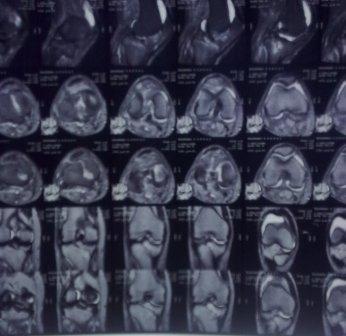

Здравствуйте уважаемые коллеги!Сегодня обратился больной 35л. Травму получил 3 мес.назад, упал в яму, лечился в отдаленном районе гипсовой повязкой, 1 месяц назад гипс сняли , и больной начал ходить с нагрузкой, постепенно появилась деформация коленного сустава, неустойчивость и боли. Локально: деформация коленного сустава, голень смещена кзади- типа подвывиха, разгибание 170гр. Сгибание 150гр.симптомов повреждение коллатеральных и крестообразных связок определить не удается из-за боли и контрактуры. Первичных снимков пока нет, обещали принести, имеется снимки через 2 месяца после травмы без гипса, недельной давности снимки в прямой проекции и К Т. Похоже, что импрессия переднемедиальной части внутреннего мыщелка б/берцовой кости, отрыв межмыщелкового возвышения.

Оперировать нужно,наверно после разработки-проведение остеотомии большеберцовой кости.Да, Вы так же думаете.Я бы,1-ым этапом, провел санацию коленного сустава-возможно мешает поврежденный наружный мениск,это можно сделать и сразу,не ожидая восстановления объема движений,конечно лучше артроскопом.Дообследования о возможном характере внутрисуставных повреждений(УЗИ,ЯМРТ)я понимаю не проведено.Есть возможность?-Сделайте,проще будет планировать вмешательство.

На снимке типичный перелом медиального тибиал плато с передним смещением (подвывих) по Schatzker IV. Консервативное лечение без медиальной опоры не может удержать деформирующие силы, и из-за вторичного смещения мыщелка конечность смещается в варус. Кроме передних смещений еще встречаются сложные фронтальные варианты переломов, и тогда голень подвывихивается кпереди.

А в данном случае мыщелок сросся со смещением кпереди и ротирован. За счет интактной наружной колонны опороспособность конечности сохранена, но остается варус и экстензия конечности. Для предоперационного расчета необходимо сделать на всю длину конечности рентгенограмму, а в остром периоде КТ и 3-мерный снимок помогут лучше ориентироваться в характере перелома.